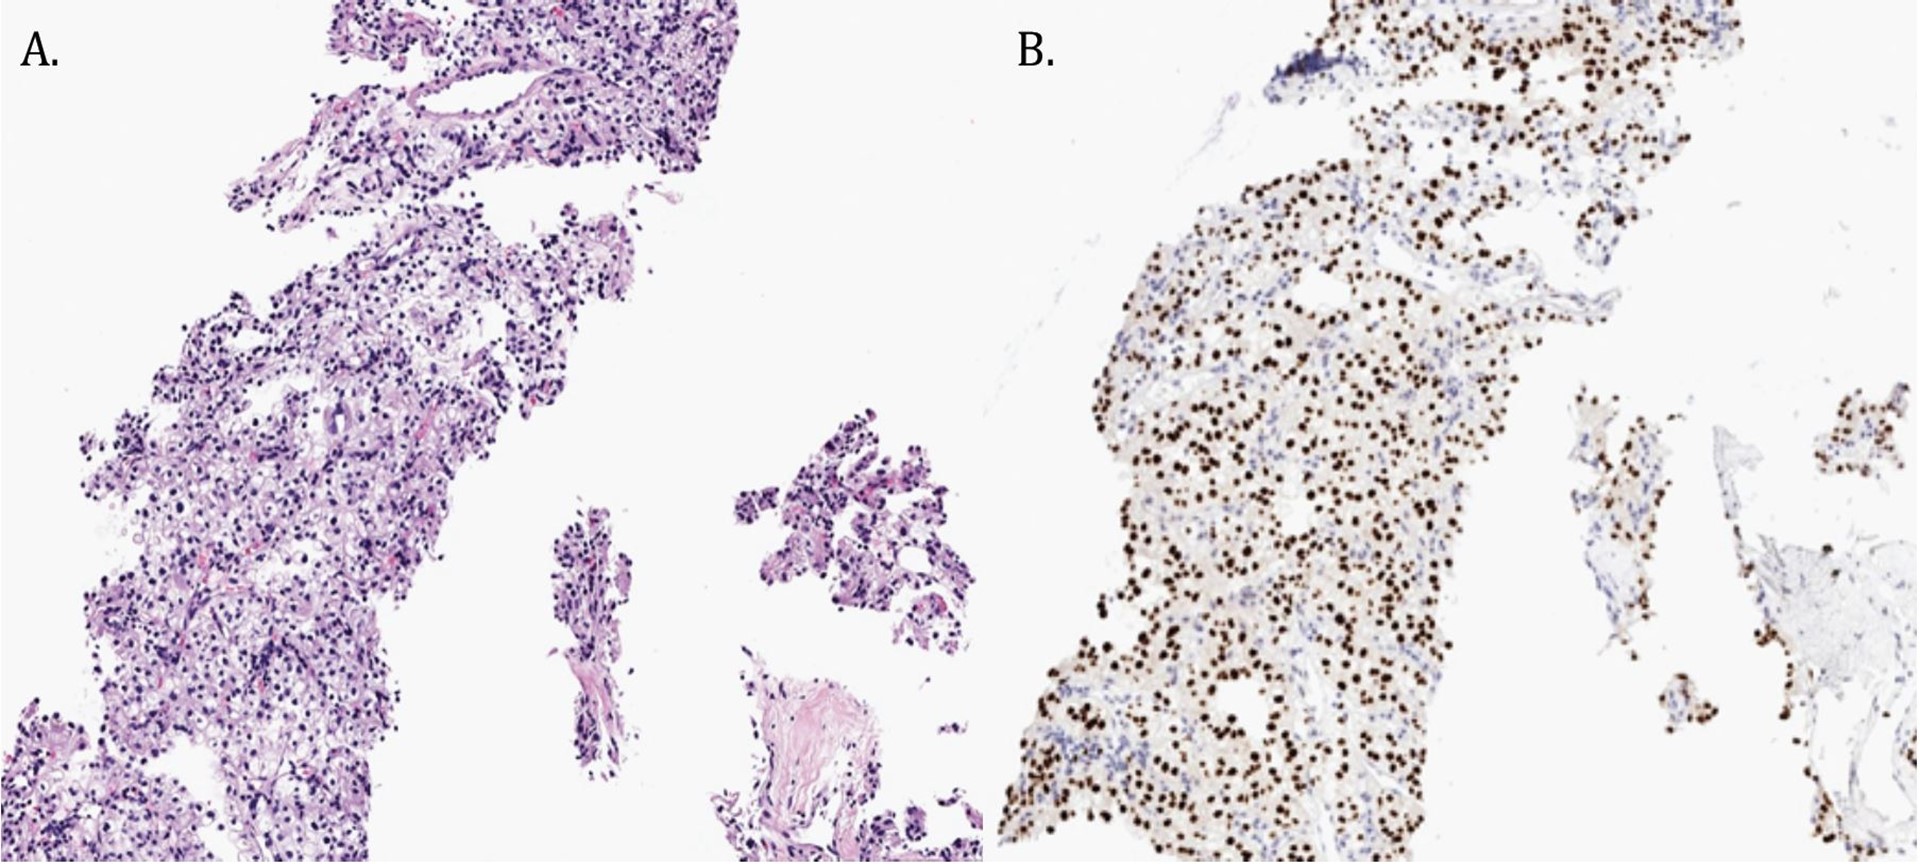

Work-up of the right chest wall mass included a CT chest which demonstrated an expansile destructive right rib lesion measuring 5.8 x 4.1 x 6.5 cm and a nonspecific 3mm pulmonary nodule (Figure 1). A CT-guided biopsy of the chest wall mass was most consistent with clear cell RCC (Figure 3). Subsequent CT of his abdomen demonstrated a 3.9 x 4.2 x 4.0 cm heterogenous exophytic right renal mass (Figure 2). The patient denied gross hematuria, unintentional weight loss, constitutional symptoms, and pain. His physical exam was remarkable for a palpably firm right chest wall mass, and lab data revealed normal serum hemoglobin, absolute neutrophil count, platelets, and calcium. With his excellent performance status and normal lab results he was assigned to the intermediate risk group as per the International Metastatic RCC Database Consortium (IMDC) prognostic model13. Notably, he had mild baseline chronic kidney disease with a serum creatinine of 1.5 and an estimated glomerular filtration rate was 48.2 ml/ min/1.78 m2.

Histopathologic examination of the partial nephrectomy specimen revealed a 5.5 cm clear cell RCC with negative surgical margins, Fuhrman Grade 3. Metastatic RCC was present in the right lower lobe wedge (0.25cm) as well as the chest wall resection (7.4cm) which involved bone, skeletal muscle, and fibroadipose tissue (Figure 4). All surgical margins were negative, and a pathologic stage of pT1bNxM1 was assigned.